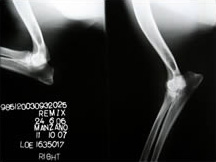

Codos: Libre

Ch. Remix de Pomerland - Codo Derecho

Ch. Remix de Pomerland - Codo Izquierdo